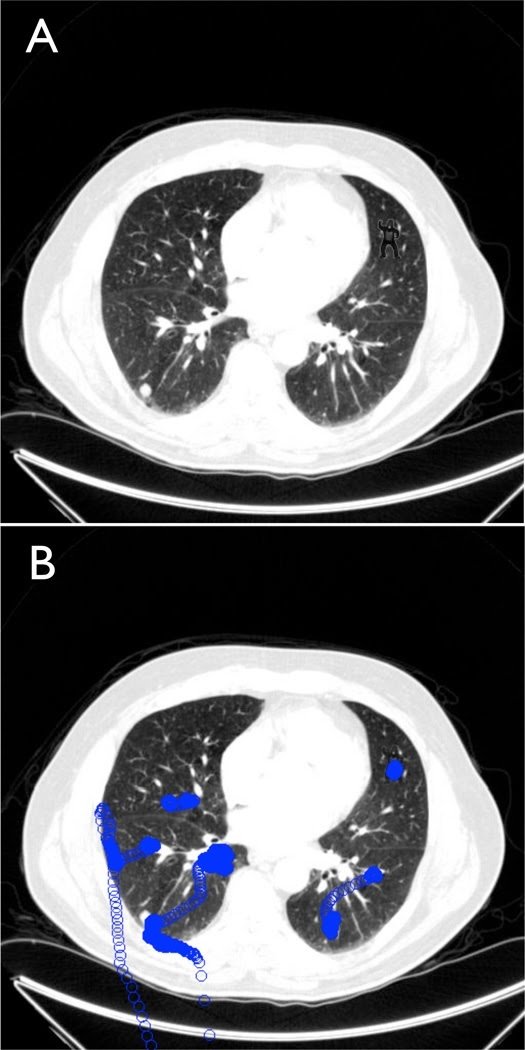

Este efecto de la ceguera inatencional resulta de lo más divertido cuando experimentamos con un tipo disfrazado de gorila, pero puede impactarnos cuando lo trasladamos a decisiones en el mundo real. Por ejemplo, al trabajo cotidiano de los radiólogos4. En un experimento en 2013 de Drew y colaboradores, los investigadores pidieron a 24 radiólogos que escanearan diferentes imágenes con el objetivo de localizar en ellas nódulos cancerígenos.

Lo que no sabían los especialistas es que estas imágenes escondían también la figura de un pequeño gorila. Veinte de ellos, el 83%, no llegaron a detectar al gorila. Fueron ciegos a lo que no atendieron.

Imagen de Drew y colaboradores (2013)5